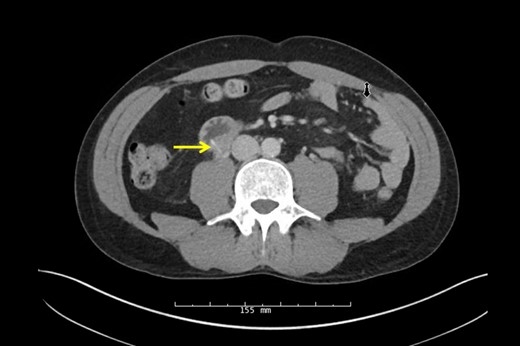

A 38-year-old male presented to the hospital with a chief complaint of abdominal pain and hematuria 1 day after eating a barbecue pulled pork sandwich. He described the pain as ‘deep’ in his abdomen, sharp and non-radiating with no episodes of nausea, emesis or diarrhea. He denied any dysuria or frequency. The patient's past medical and surgical history was unremarkable. He had no abnormalities on his laboratory values besides a urinalysis demonstrating 2+ blood and 11–24 RBCs/hpf. Physical examination revealed point tenderness to deep palpation to the right of his umbilicus, but his abdomen was soft with no signs of peritonitis. An upright abdominal X-ray was unremarkable; however, a CT of his abdomen demonstrated a 2-cm linear density representing the FB in the posterior third portion of the duodenum perforating into the retroperitoneum abutting the right ureter causing hydronephrosis (Figs 1 and 2, arrow). Two separate attempts were made at endoscopic retrieval in the first 24 h without successful visualization or removal of the FB. Due to the ureteral involvement and hydronephrosis, an operative intervention was recommended.

Sagittal CT scan again demonstrating the FB through the posterior wall of the duodenum onto the anterior surface of the ureter.